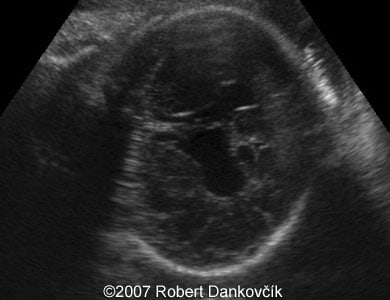

Images 3, 4: 2D sonography; 32 week of pregnancy; coronal planes through the fetal skull showing dilated lateral ventricles and interhemispheric cyst extending to the right.

3

4